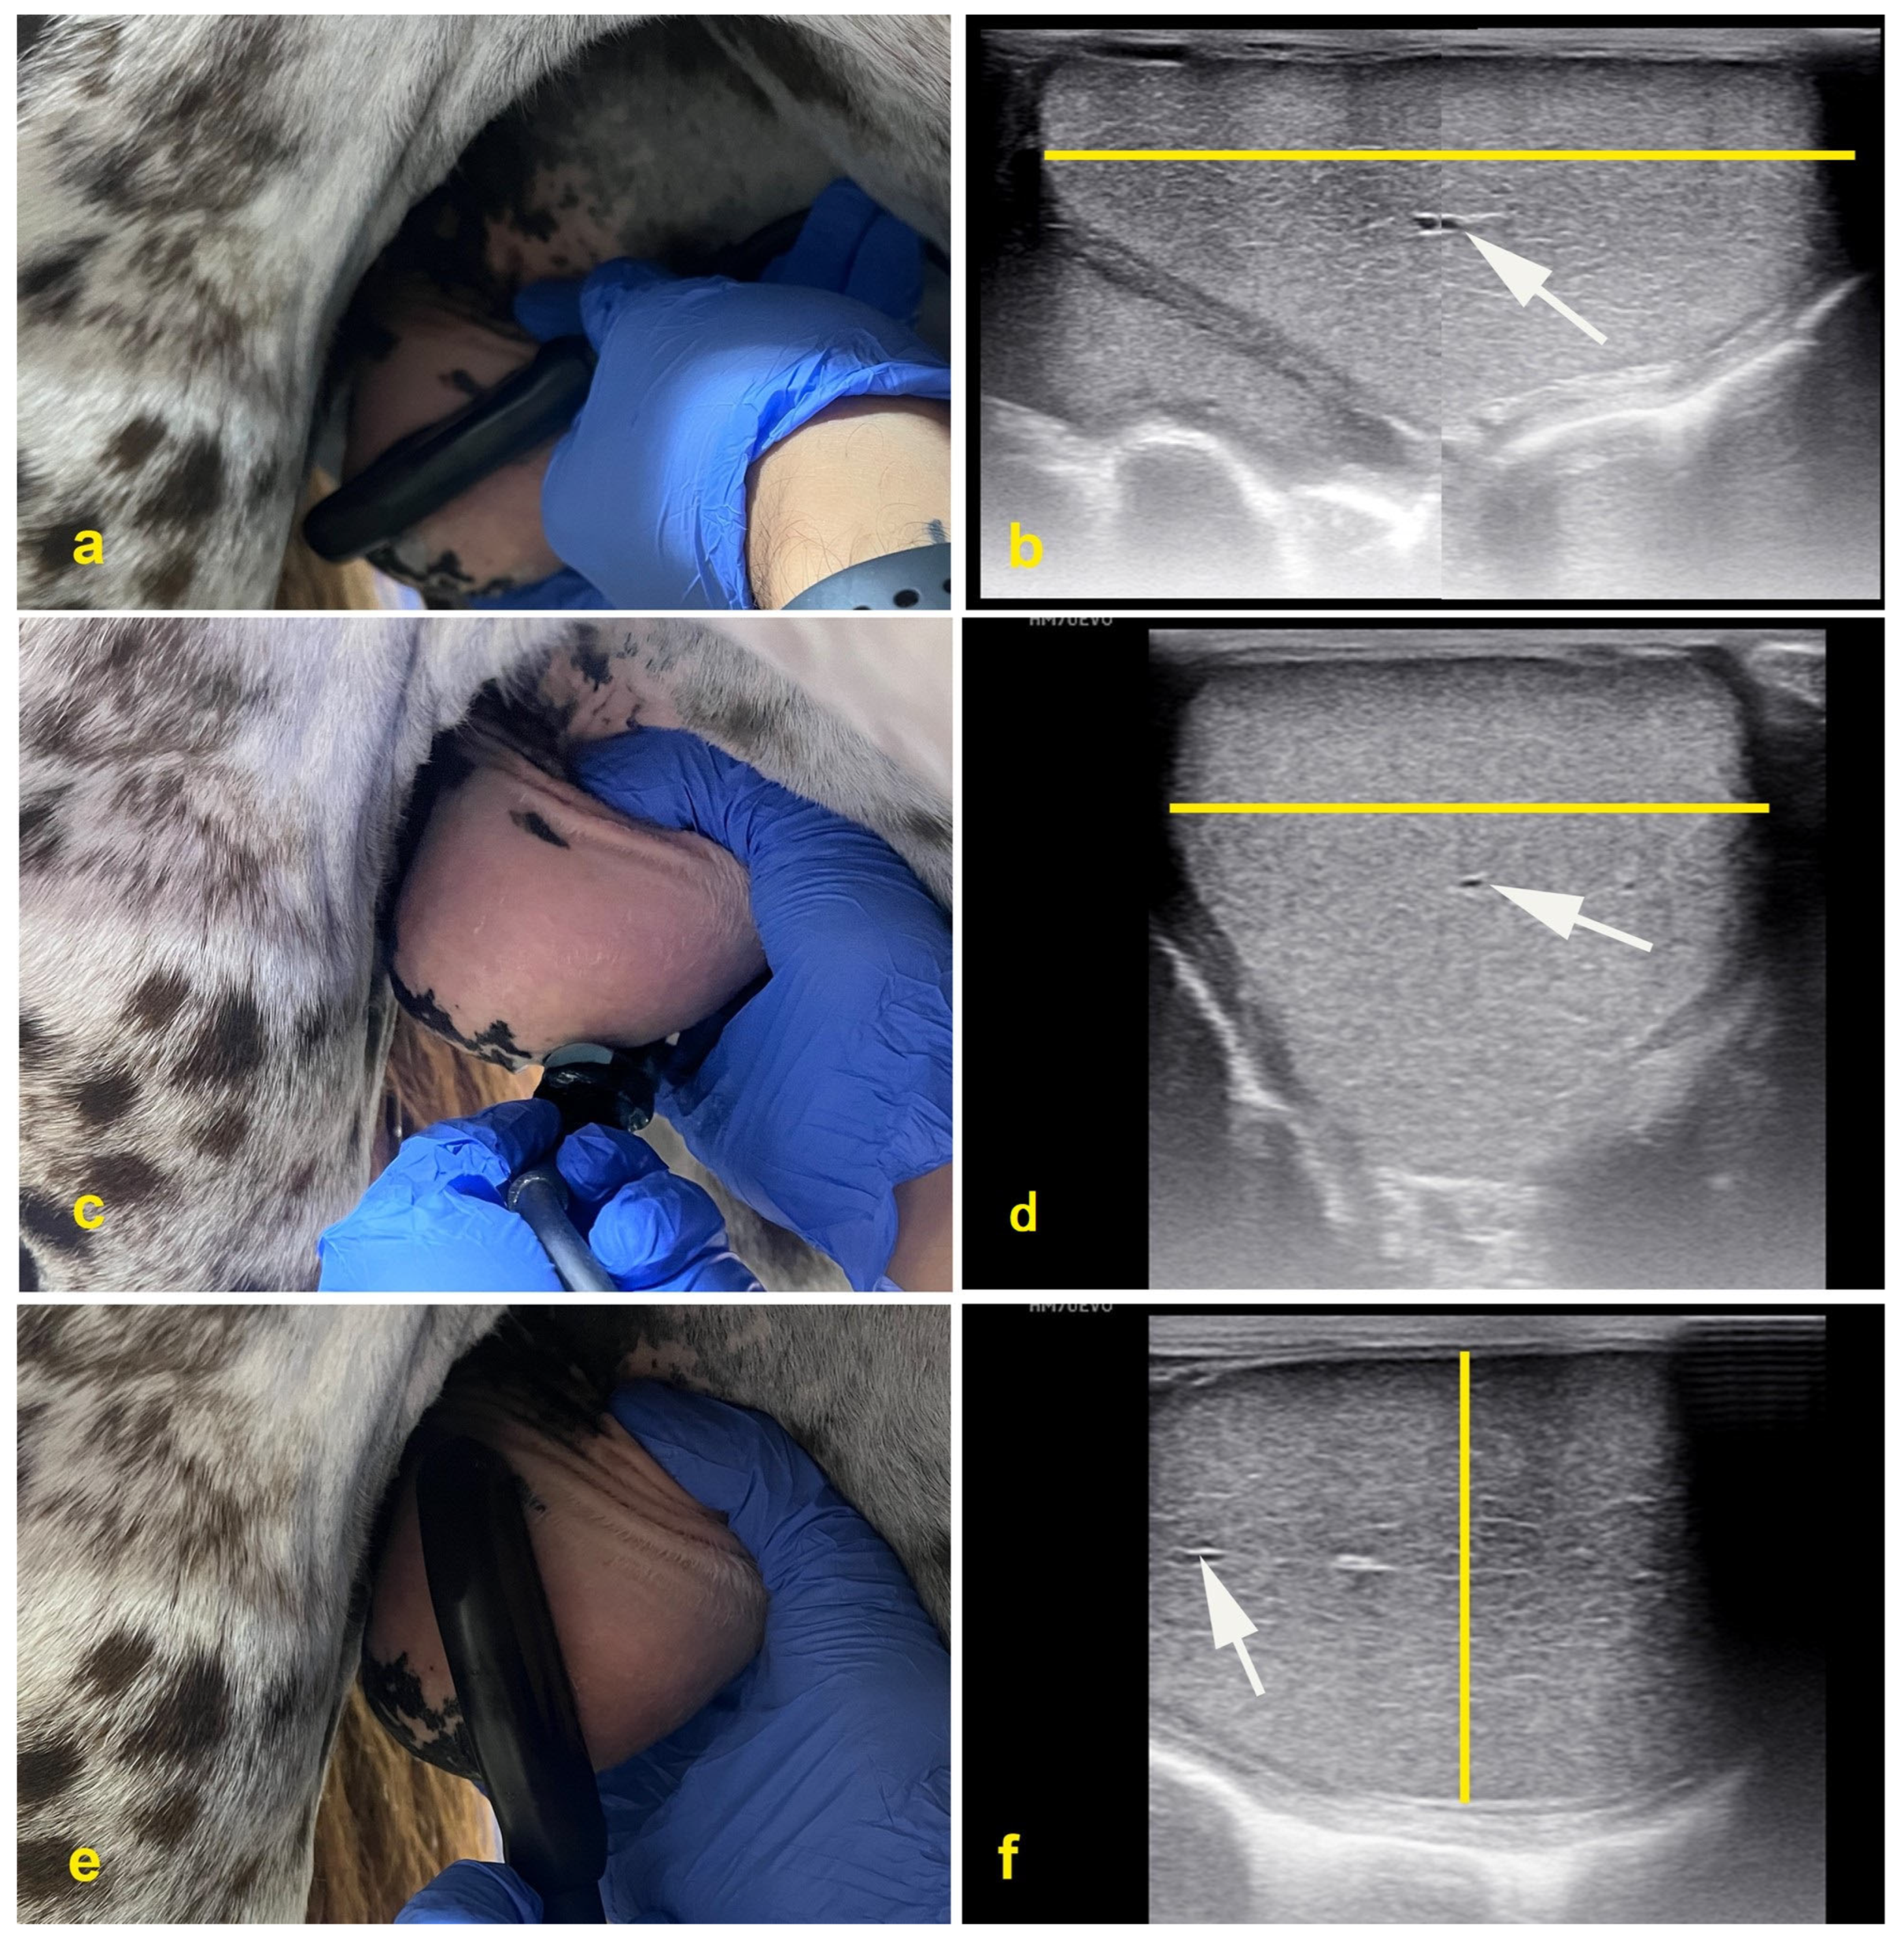

2.5. Fine-Needle Aspiration

2.6. Testicular Biopsy